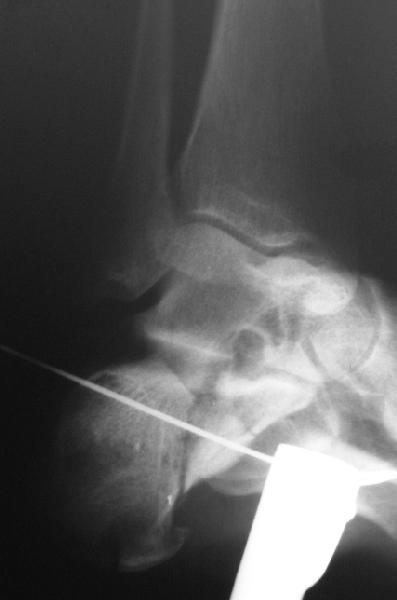

В/суставные переломы пяточной кости у молодых являются показанием к оперативной коррекции, Большой материал накоплен у д-ра Дрягина (Челябинск). В нашем отделении предпочтение отдаем открытой репозиции, при наличии выраженного отека, фликтен и т.д.

Накладываем спицевой дистрактор, позволяющий выхаживать м/ткани и одновременно устранять захождение отломков.

Окончательная фиксация спицами, пяточными пластинами (5) , в последнее время стали применять крючковидные пластины (ДЕОСТ) (6,6a).

Кроме стандартных снимков, необходим контроль конгруэнтности суставной поверхности (проекции Бродена)